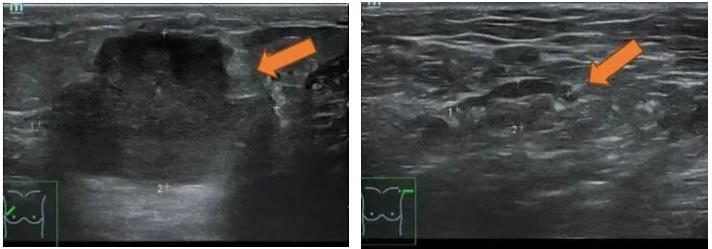

2021.7.6 钼靶示:右乳外上象限肿块,考虑乳腺癌(BI-RADS-5类)右腋下肿大淋巴结,M灶可能。

右乳外上象限不规则高密度肿块,边缘毛糙,大小约3.3×2.7cm,邻近皮肤牵拉增厚,右腋下见肿大淋巴结。

图2. 钼靶

(3 cycle 后)2021.9.21 钼靶示:右乳外上象限不规则形肿块明显缩小,右腋窝淋巴结亦较前缩小。

图6. 钼靶